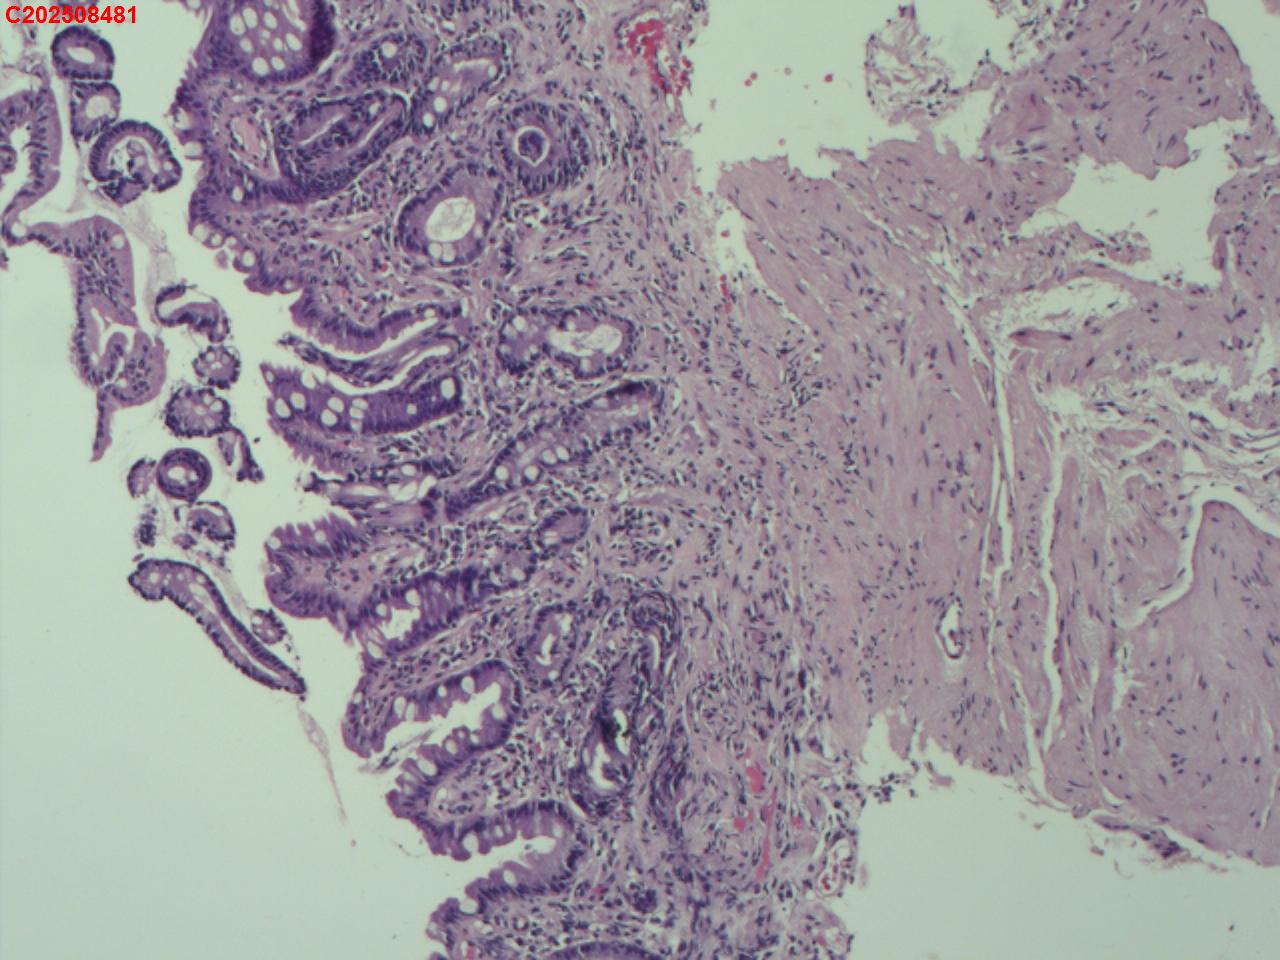

胃窦粘膜

性别

男

年龄

66岁

临床诊断

门脉高压性胃病伴糜烂

一般病史

肝硬化

标本名称

大体所见

粘膜多发片状充血、糜烂。

图2

慢性萎缩性炎,伴肠化,